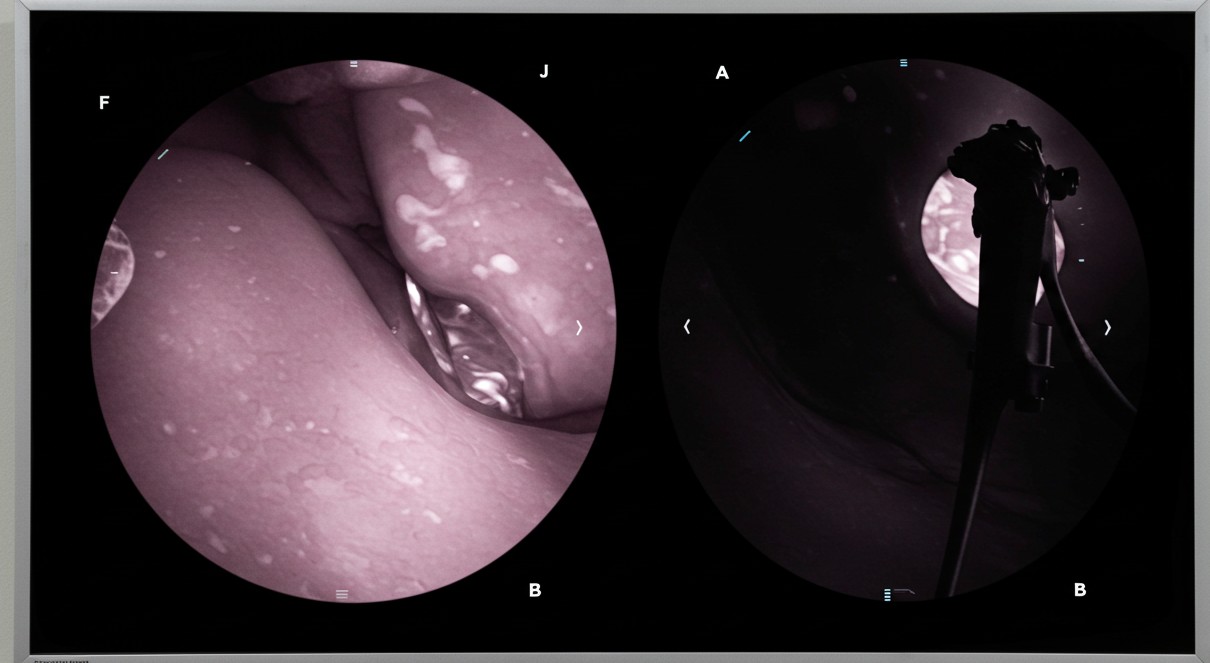

- 검진 방법: 위내시경 권고 (기본 검진 방법으로 확정)

- 위장조영촬영: 위내시경이 어려운 경우에만 제한적 허용

이는 위내시경이 조기 위암 발견에 가장 효과적이라는 국내외 연구 결과를 반영한 것입니다.